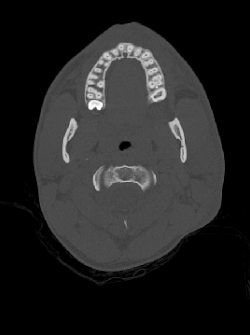

Računalna tomografija

Računalna tomografija ili skraćeno CT (engl. Computed tomography) računalna je rekonstrukcija tomografirane ravnine tijela. Slikovna je radiološka metoda koja nam daje slojevni prikaz pregledavanog dijela tijela, a za nastanak slike rabi se ionizirajuće rengensko zračenje.

Suvremena radiologija sve više primjenjuje digitalne sustave za dobivanje slike ljudskog tijela koji postupno zamjenjuju analogne uređaje u kliničkoj praksi. Digitalna tehnologija se odavno primjenjuje kod slojevnog snimanja, a početak takvog slikovnog zapisa se može pripisati računalnoj tomografiji. Danas je većina ultrazvučnih skenera također digitalizirana. Oslikavanje ljudskog tijela pomoću magnetske rezonancije je nezamislivo bez digitalne konverzije analognog signala.

U radiološkoj dijagnostici zrače uređaji za rendgensko snimanje (primjerice, za snimanje kostiju ili pluća), uređaji za dijaskopiju (primjerice za pregled želuca, irigografija) i uređaji za računalna tomografiju (CT). Magnetska rezonancija i ultrazvuk ne koriste štetno ionizirajuće zračenje za oslikavanje ljudskoga tijela. Ipak, magnetska rezonancija može biti opasna kod metalnih stranih tijela ili ugrađenog pace-makera. Nažalost, niti jedna od metoda ne pokriva sve dijagnostičke potrebe. Odabir dijagnostičke pretrage treba prepustiti liječniku koji će odrediti najkraći put do točne dijagnoze, uz najmanju štetu za zdravlje bolesnika.